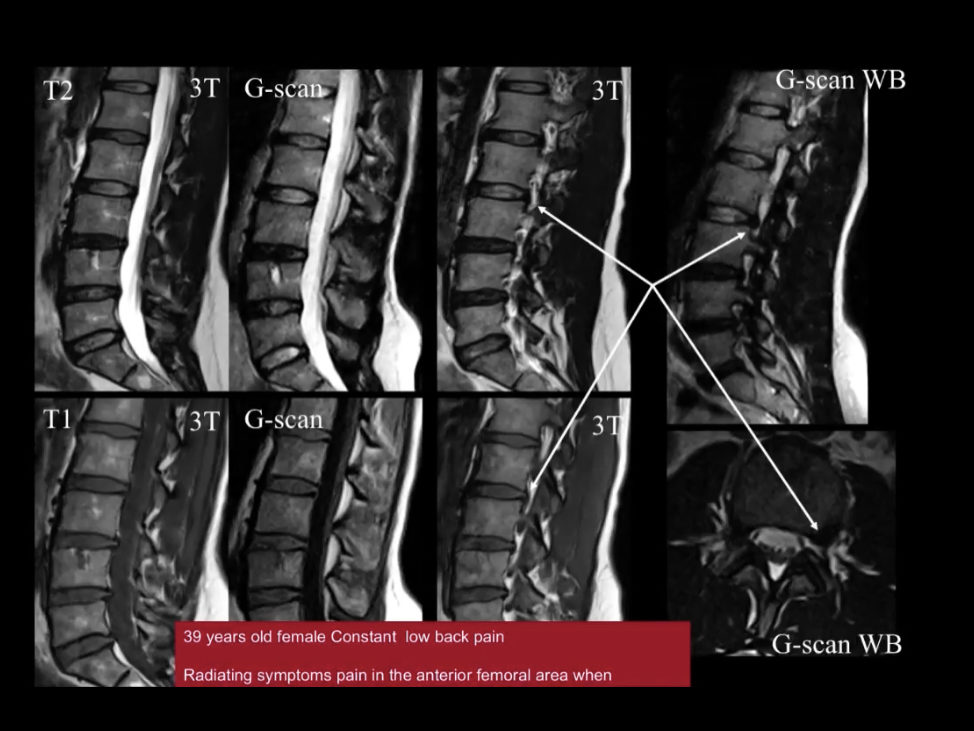

Unique Weight-bearing MRI Capabilities

Weight-bearing studies are easy to perform, allowing patients to be images in the position in which they experience symptoms and providing documentation that can be critical in pre-surgical workflow.

Thanks to a combination of dedicated MSK sequences, advanced RF coils, and patented computing technology, Esaote MRI systems deliver high-quality MSK images in line with today’s throughput constraints.

Weight bearing MRI provides optimal diagnosis of lumbar disc herniation – Reno, Sparks, Carson